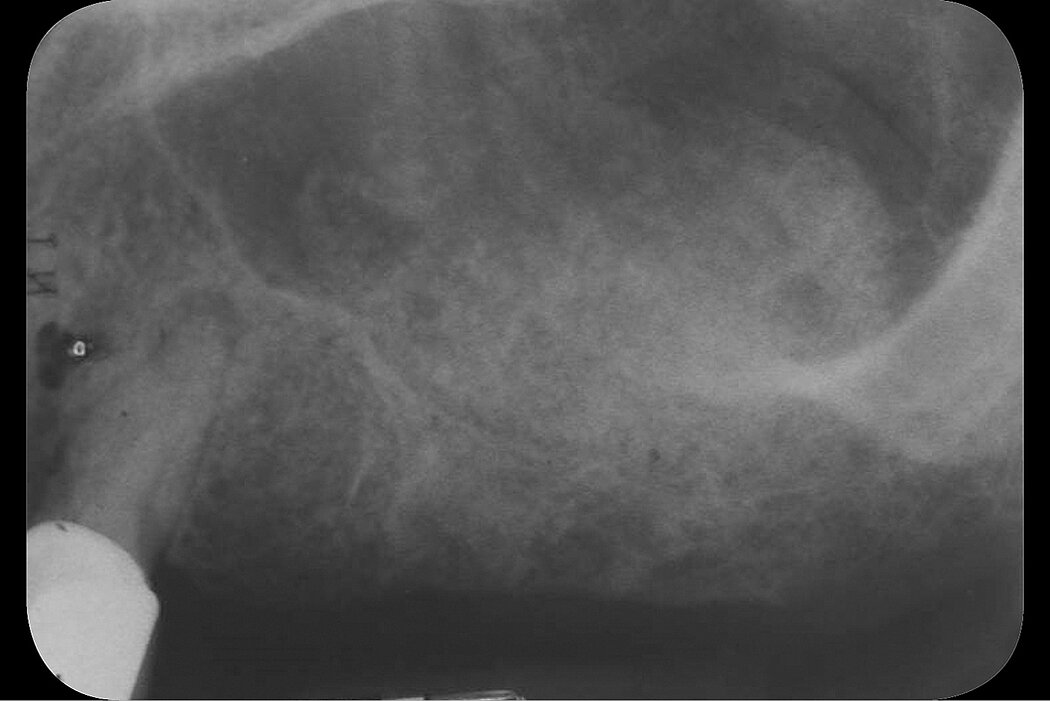

一位中年男性来到诊所要求种植修复。全景放射线片显示右上颌窦有朦胧阴影。实施锥形束CT扫描(CBCT)进一步评估,存在一射线不能透过的穹状区域。放射学光片显示上颌窦内假性囊肿。在第一磨牙区域,剩余骨高度足以避免使用侧壁开窗方法。但是第一磨牙区残留牙槽嵴的形态和窦假性囊肿的存在对于经牙槽嵴顶上颌窦底提升并不是有利的指标。

为了确认射线不透性是无症状的窦假性囊肿,计划通过侧壁开窗进行上颌窦底提升。打开一个骨窗后,可以抽出带有淡黄色囊液的小囊性病变。手术过程中发现了上颌窦膜穿孔,用Geistlich Bio-Gide®成功修补。